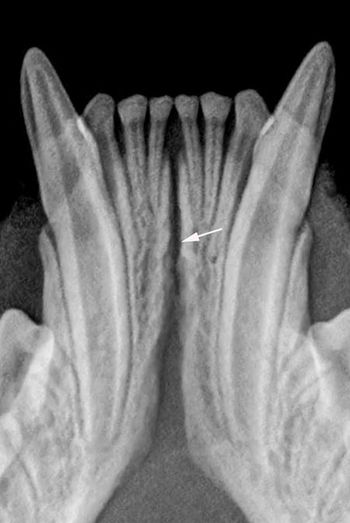

You see a possible lesion on a veterinary patient's dental film-here's how to tell if it's the real thing.

Intraoral radiography can help identify this pathology in your patients-and guide you toward the next step in your treatment plan.